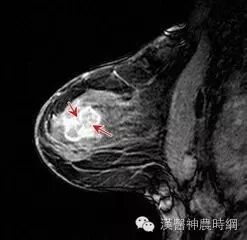

這些情況可能易患乳腺癌?

乳腺癌

哪些女性容易患乳腺癌

乳房赋予了女人特有的美丽及性感,也使女性易患上乳腺癌。但是到底哪些女人容易罹患乳腺癌呢?

(一)35~55岁为乳癌好发年龄

一般认为乳腺癌与卵巢功能、遗传因素、婚育及哺乳等因素有密切关系。因此乳腺癌主要发生于青春期以后的成年妇女,35~55岁为好发年龄,有以下情况就要谨防乳腺癌的发生。